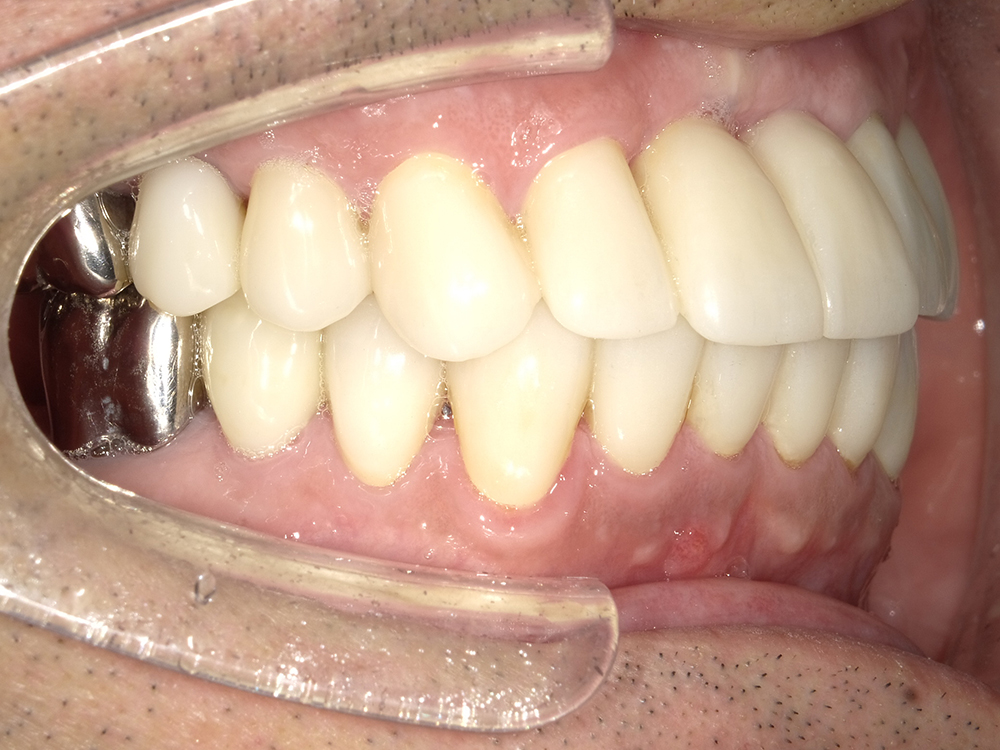

55歳 男性

- 主訴

- 前歯でしか咬めなく、食事を採るのに非常に困難で辛い

- 処置内容

- 上顎6本、下顎3本

- 治療費用

- 上顎:約230万(税込)下顎:約120万(税込)

- 治療期間

- 上顎:1年(仮歯まで8か月)下顎:8か月(仮歯まで5か月)

- リスク

- 上部構造物、仮歯の破折、術後の腫れ(3日)、人工歯根脱落リスクがあります